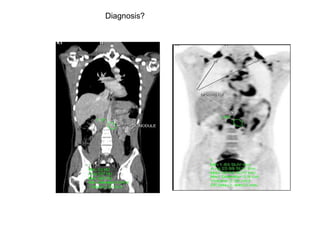

GIT TUMOUR

Diagnosis?